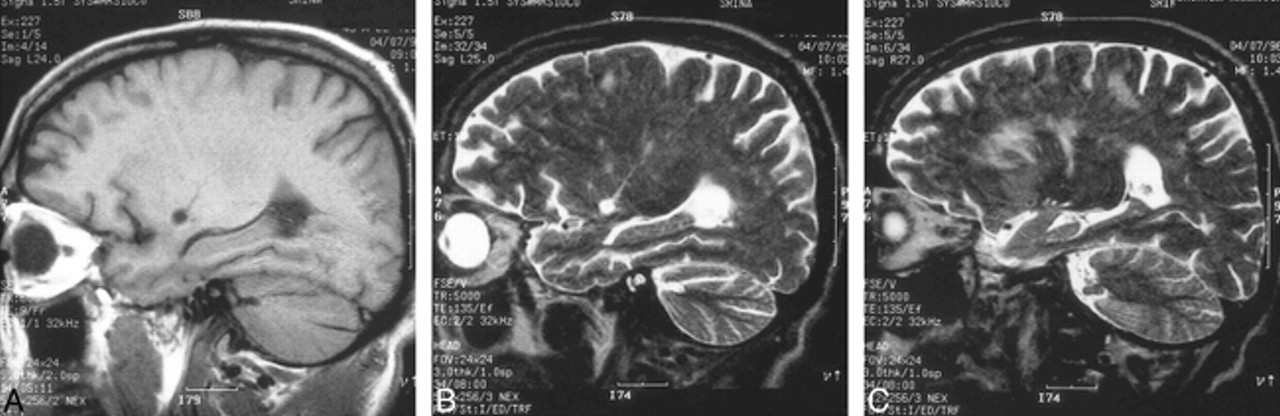

Semptomların gövde ve kollara yayılması ve baş ağrılarının şiddetlenmesi üzerine ikinci kez hastaneye başvuran kadının kan testlerinde, bağışıklık sisteminin parazitlere karşı tepkisini gösteren eozinofil adı verilen beyaz kan hücrelerinin sayısında artış tespit edildi. Bunun üzerine beyin omurilik sıvısından örnek alındı ve eozinofilik menenjit teşhisi konuldu. Bu nadir görülen beyin ve omurilik iltihabının en yaygın nedeni, "rat lungworm" olarak bilinen Angiostrongylus cantonensis parazitidir.

Angiostrongylus cantonensis, genellikle Güneydoğu Asya ve Pasifik Adaları'nda, özellikle Hawaii'de bulunan bir parazittir. Parazitin yaşam döngüsü, kemirgenler ve ara konakçı olan salyangozlar veya sümüklü böcekler arasında gerçekleşir. İnsanlar, bu enfekte ara konakçıları çiğ veya az pişmiş olarak tükettiklerinde veya kontamine olmuş sebzeleri yediklerinde enfekte olabilirler. Parazit, insan vücuduna girdikten sonra merkezi sinir sistemine ulaşarak baş ağrısı, ense sertliği, bulantı, kusma, karışıklık ve bacaklarda yanma hissi gibi semptomlara yol açabilir.